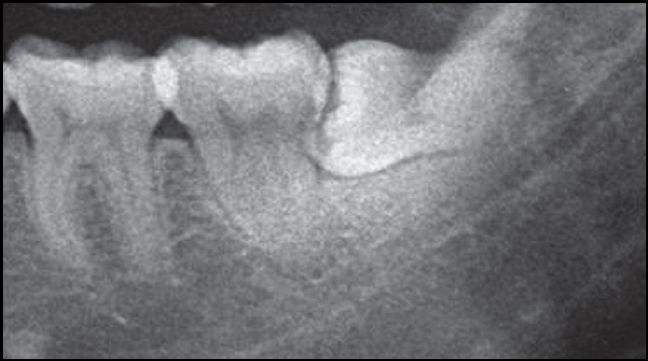

综上所述,拔牙时的阻力主要为邻牙阻力、冠部阻力、根部阻力。有的阻生智齿可同时存在邻牙阻力、冠部阻力、根部阻力。

阻力存在的不同情况

A.邻牙阻力

B.远中冠部阻力

C.根肥大根部阻力大

D.邻牙阻力、冠部阻力和根部阻力同时存在